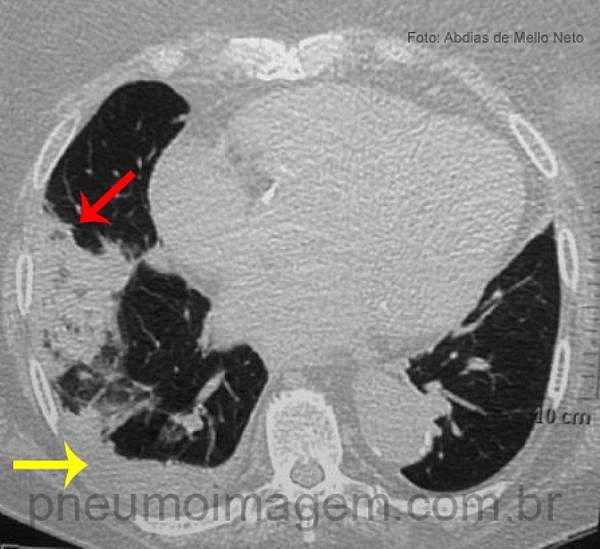

Novas diretrizes para tromboembolia pulmonar (TEP) sugerem que a tomografia computadorizada (TC) e o teste de dímero-D no plasma são realizados de modo excessivo em pacientes com suspeita de embolia pulmonar e podem fazer mais mal do que bem. O American College of Physicians (ACP) publicou as diretrizes online em 29 de setembro no Annals of Internal Medicine.

Testes de dímero-D são mais apropriados para doentes com risco intermediário para TEP e nenhum teste pode ser necessário para alguns pacientes de baixo risco. Nenhuma evidência existe que o maior uso de TC para a avaliação de pacientes com suspeita de embolia pulmonar levou a melhores resultados dos pacientes. Os potenciais malefícios de exame de imagem desnecessário incluem os custos, o aumento da exposição à radiação, e seguimento para achados incidentais. Os autores recomendam usar tanto as regras de Wells ou de Genebra para escolher quais exames realizar em um paciente de risco para embolia pulmonar.

Pacientes de alto risco devem ignorar o teste de dímero-D e prosseguir com a investigação por angio-TC pulmonar, porque um exame de dímero-D negativo não vai eliminar a necessidade de imagem nesses pacientes. Os médicos só devem indicar exames de ventilação-perfusão em pacientes com contra-indicação para angiografia pulmonar ou se angiotomografia pulmonar não está disponível.